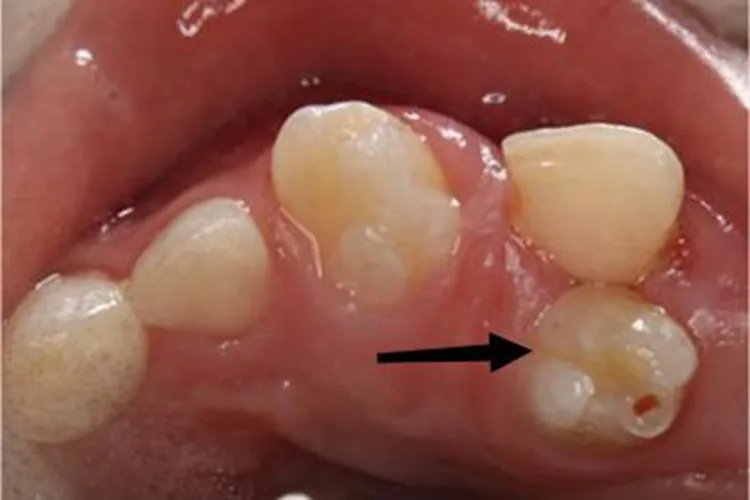

概述多生牙可导致牙齿增多,而且形态呈圆锥形、结节形等,病因不清,与发育缺陷、遗传有关,已经萌出者应由医生及时拔除。症状多生牙可表现为牙齿增多,而且形态变异,可呈圆锥形、结节形等,表面光滑,颜色与正常牙齿无异,常可造成牙列拥挤、牙间隙大、牙移位等症状。

病因多生牙是胚胎时期由于各种因素的影响,使得颌面部生长发育的某一阶段出现异常,也就是来自牙胚发育的起源和增殖阶段的异常所致。本病的具体病因不清,与发育缺陷、遗传有关,属于常见的先天性牙颌发育畸形。治疗对于已萌出的多生牙应及时拔除,拔除需由专业医生操作。如多生牙埋伏在颌骨内,应追踪观察。如未对恒牙产生影响,且无任何病理变化时,可不做处理。如果埋伏多生牙位于年轻恒牙根尖附近,拔除时可能会伤及恒牙根部,则可暂不处理,待年轻恒牙牙根发育完成后再拔除。如果多生牙造成正常牙的牙根吸收或牙根弯曲畸形、移位,而多生牙形态类似正常牙、牙根有足够长度者,可考虑保留多生牙,拔除正常牙。